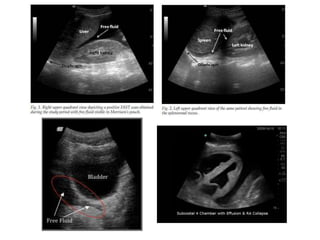

– Bedside sonography should be used to perform an

FAST exam (figure 1).

In the setting of hypotension, free fluid on the FAST exam

surgical intervention (see figure 2)

trauma (FAST) examination

– A widely accepted primary diagnostic study.

– Many clinically significant injuries will be associated

with free intraperitoneal fluid.

– Rapid identification of free intraperitoneal fluid in the

hypotensive patient with blunt abdominal trauma.

Since the FAST examination can reliably detect small amounts of free

intraperitoneal fluid and can estimate the rate of hemorrhage through

serial examinations, it has essentially replaced diagnostic peritoneal

lavage (DPL) for blunt abdominal trauma in the majority of North

American Trauma Centers

• Increasingly used in the ED resuscitation

room to

– Assess the chest and abdomen of acutely injured

patients, especially those with shock.

• Can be performed by a trained ed doctor,

surgeon, or radiologist.

hand-held USS scanner.

Looks at four areas for the presence of

free fluid only:

• Hepatorenal recess (Morrison’s

pouch).

• Splenorenal recess.

• Pelvis (Pouch of Douglas).

• Pericardium.

The scan is usually done in that order,

as the hepatorenal recess is the first to

fill with fluid in the supine position, and

is most easily identified.

Free fluid appears as a black echo-free area:

• Between the liver and the right kidney.

• Between the spleen and the left kidney.

• Behind the bladder in the pelvis.

• Around the heart in the pericardium.

A POSITIVE FAST SCAN

• Is one which identifies any free fluid in the abdomen or in the pericardium.

• Visible free fluid in the abdomen implies a minimum volume of ≈ 500ml.